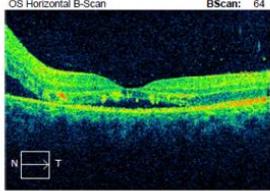

On examination, his visual acuity in the right eye was 6/4.5 while his left eye was counting fingers. His intraocular pressures were $16\mathrm{mmHg}$ and $10\mathrm{mmHg}$ in his right and left eye respectively. He had a grade III left relative afferent pupillary defect (RAPD). Whilst he had full range of eye movement, there was pain on moving his left eye. His left optic nerve was grossly swollen with a macular star (figure 1). There was no anterior chamber inflammation or vitritis. Optical coherence of the retinal nerve fibre layer (OCT RNFL) assessment showed an average RNFL thickness of $481\mu \mathrm{m}$, with peripapillary subretinal fluid extending to the fovea (figure 2). Automated perimetry demonstrated an early central scotoma in the left visual field with mean deviation (MD) -4.35 dB. He had a normal right ocular examination and ancillary investigations. Clinical examination and investigations were consistent with left neuroretinitis.

Figure 2: Zeiss OCT macular $512 \times 128$ cube (a) and disc RNFL $200 \times 200$ cube (b) of both eyes. The left eye demonstrates optic nerve head oedema (b) with peripapillary and foveal subretinal fluid (a).